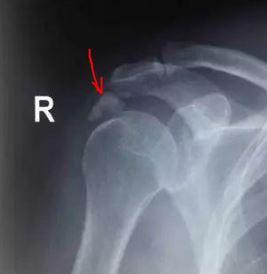

X线提示:肱骨头上方钙化灶